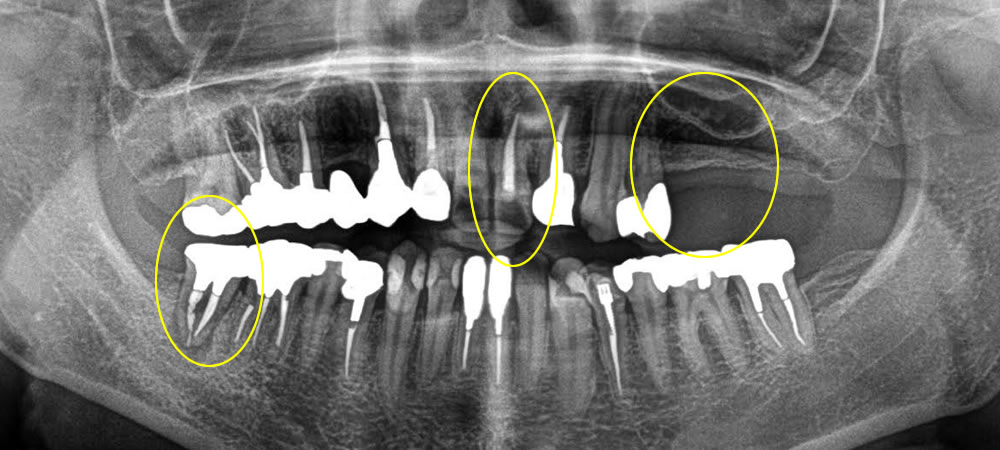

保存不可能な歯を抜歯即時インプラントで治療した症例

こちらの患者さまは、前歯がグラグラ揺れて痛い、右下奥歯が痛い、左側で噛む事ができるようになりたいとの主訴で来院されました。保存する事ができない歯にインプラント治療を行いたいというご希望でしたので、相談しながら治療計画を立案しました。

まず一番時間がかかる歯から治療を行ないました。保存不可能な右下奥歯を抜きインプラントを埋入し、骨がなくならないよう骨造成を行いました。次に前歯のインプラントを行いました。前歯は審美性もより考えて行うため、歯を抜きインプラントを埋入し、特殊な縫合を行い歯茎をしっかりと閉じていきました。最後に元々歯のないところにインプラントを埋入していきました。こちらは骨が元々ある場所なので、切開を最小限に抑え1本に対して6ミリ程度の切開幅でオペを行いました。それにより、術後の腫れ、痛みを最小限に抑える事ができました。

しっかりと骨とインプラント体が結合するのを待つため、5ヵ月待機した後に上部に歯を作成していきました。結果、審美的回復、機能的回復をする事ができました。